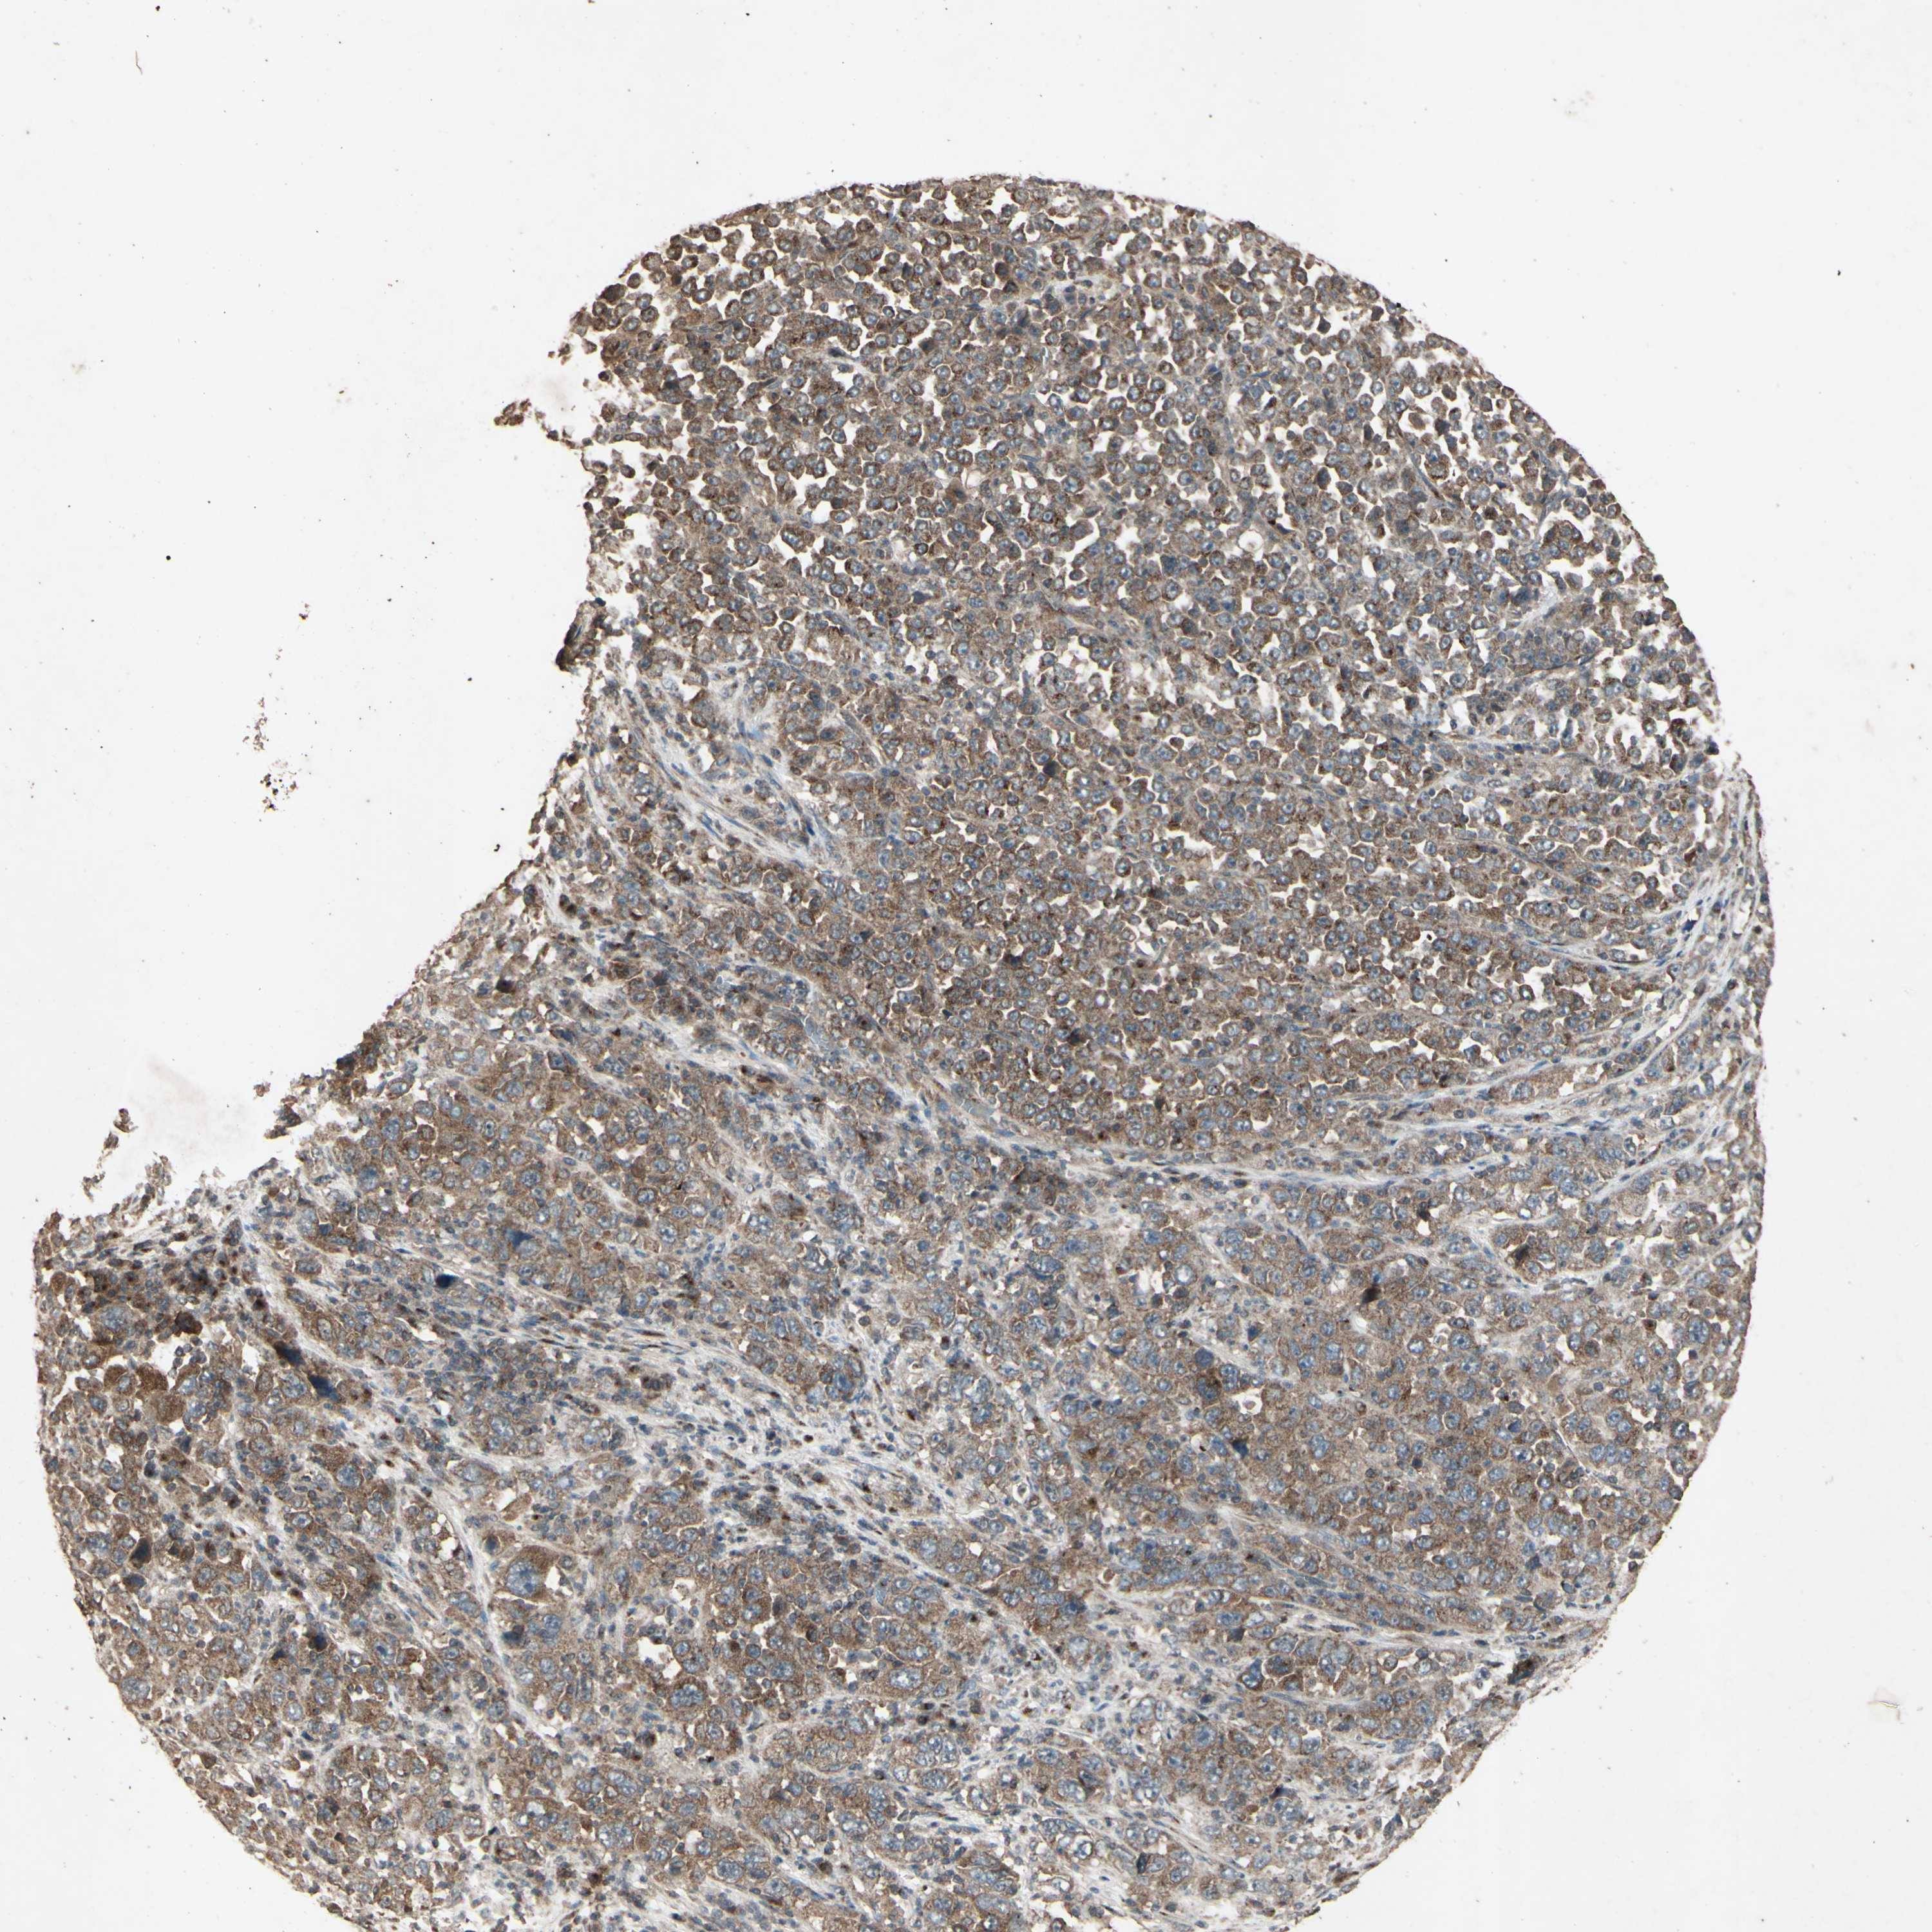

STOMACH CANCER - Protein expressioni

A mouse-over function shows sample information and annotation data. Click on an image to view it in a full screen mode. Samples can be filtered based on level of antibody staining by selecting one or several of the following categories: high, medium, low and not detected. The assay and annotation is described here.

Note that samples used for immunohistochemistry by the Human Protein Atlas do not correspond to samples in the TCGA dataset.

Antibody stainingi

Antibody staining in the annotated cell types in the current human tissue is reported as not detected, low, medium, or high, based on conventional immunohistochemistry profiling in selected tissues. This score is based on the combination of the staining intensity and fraction of stained cells.

Each image is clickable and will lead to virtual microscopy that enables deeper exploration of all samples and also displays staining intensity scores, fraction scores and subcellular localization as well as patient and tissue information for each sample.

Antibody CAB009049

Staining

High

Medium

Low

Not detected

Intensity

Strong

Moderate

Weak

Negative

Quantity

>75%

75%-25%

<25%

None

Location

Nuclear

Cytoplasmic/membranous

Cytoplasmic/membranous,nuclear

Adenocarcinoma, NOS

Adenocarcinoma, High grade